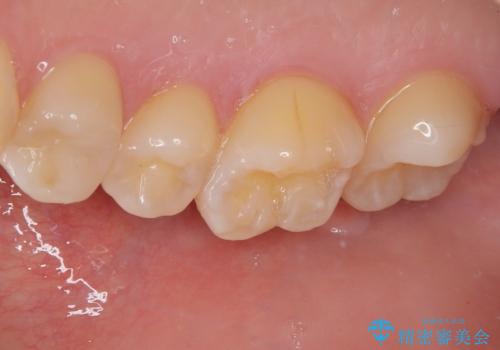

レントゲン像から、隙間のない精度の高い詰め物が入っていることが確認できます。